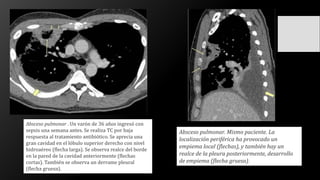

Absceso pulmonar . Un varón de 36 años ingresó con

sepsis una semana antes. Se realiza TC por baja

respuesta al tratamiento antibiótico. Se aprecia una

gran cavidad en el lóbulo superior derecho con nivel

hidroaéreo (flecha larga). Se observa realce del borde

en la pared de la cavidad anteriormente (flechas

cortas). También se observa un derrame pleural

(flecha gruesa).

Absceso pulmonar. Mismo paciente. La

localización periférica ha provocado un

empiema local (flechas), y también hay un

realce de la pleura posteriormente, desarrollo

de empiema (flecha gruesa).